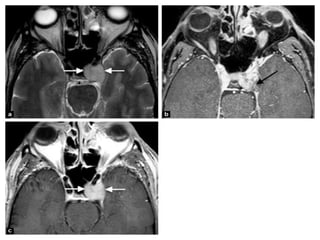

• #23 Tolosa Hunt syndrome: axial (a) and coronal (b) T2-wi, sagittal (c) enhanced CT, showing a insular hypointense enlargement of the left cavernous sinus (arrows) with an enhancement and an extension to the orbital apex (star on image c). These findings are consistent with a Tolosa Hunt syndrome.

• #24 Tolosa-Hunt SyndromeT2 iso-hypointense signal in the left cavernous sinus with enhancement Enhancement is also seen in the left superior orbital fissure